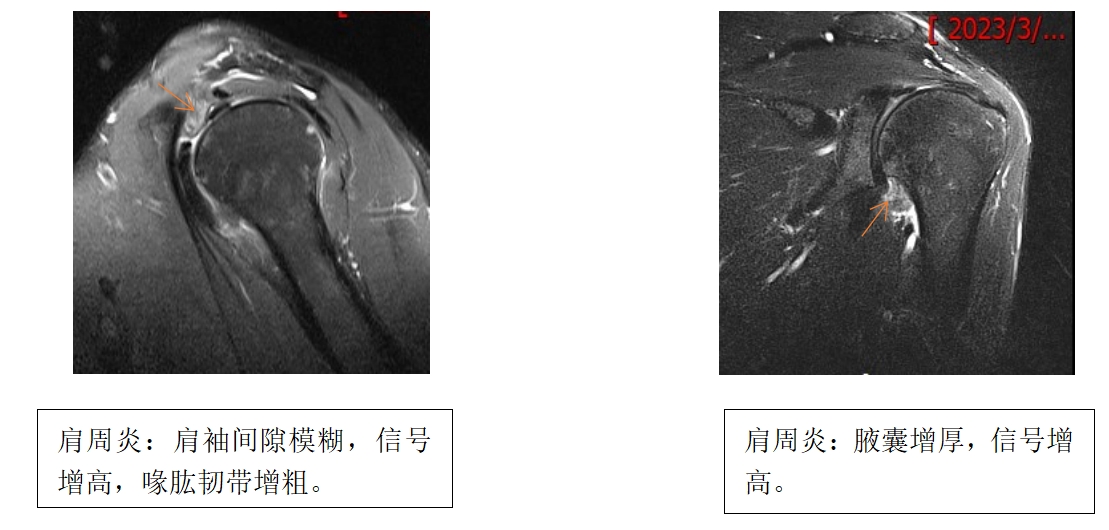

肩周炎MRI影像表現(xiàn):

喙肱韌帶、關(guān)節(jié)囊前后部及腋囊(下盂肱韌帶復(fù)合體)增厚和FST2WI/ PDW信號(hào)增高,喙突下脂肪三角閉塞,肩袖間隙處關(guān)節(jié)囊增厚、體積縮小。喙肱韌帶增厚(厚度≥4mm)對(duì)診斷粘連性肩關(guān)節(jié)囊炎具有高度特異度(95%)。